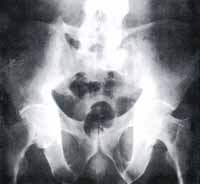

Figura 7. Radiografía de Pelvis, Proyección AP: Se observa osteopenia generalizada. Se identifica disminución regular de los espacios articulares con migración central de ambas cabezas femorales. Osteofitos “en collar” en ambos cuellos femorales. Quistes subcondrales. Puentes óseos entre L5 y ambas alas iliacas (calcificación del ligamento iliolumbar y paraarticular en la región inferior de ambas arti-culaciones sacroiliacas).